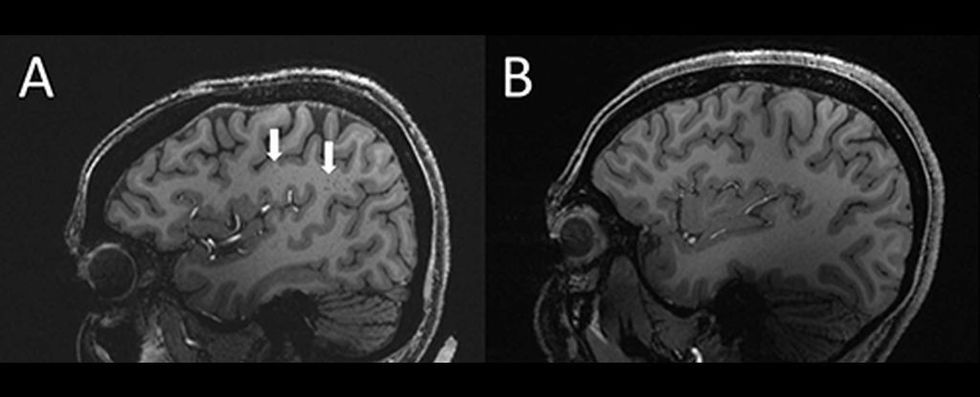

Neurologët me ndihmën e rezonancës magnetike të rezolucionit ultra të lartë kanë zbuluar që hapësirat perivaskulare – hapësira të mbushura me lëng midis enëve të gjakut dhe trurit - në mënyrë të pazakonshme janë rritur te pacientët të cilët kanë migrenë kronike dhe herëpashershme.

“Te njerëzit me migrenë kronike apo episodike, ekzistojnë ndryshime të konsiderueshme në hapësirat perivaskulare, domethënë në regjionin e trurit i cili quhet centrum simiovale”, thotë shkencëtari Wilson Xu i Universitetit të Kalifornisë Jugore në Los Angeles.

Për qëllimet e studimit të tyre, Xu dhe kolegët e tij vendosën të ekzaminojnë 20 pacientë të cilët kanë migrenë, të moshës 25 deri në 60 vjeç - 10 që kanë migrenë kronike dhe pjesa tjetër që vuajnë nga migrena të herëpashershme. Përveç tyre, si grup kontrolli janë përfshirë edhe 5 pacientë të tjerë të shëndetshëm që nuk kanë asnjë problem shëndetësor. Më pas ata kryen skanime MRI që treguan se hapësirat perivaskulare në centrum semiovale të pacientëve me migrenë ishin zgjeruar ndjeshëm në krahasim me grupin e kontrollit.

Me atë rast, u zbulua gjithashtu se kishte një ndryshim në shpërndarjen e lezionit të njohur si hiperintensitet i lëndës së bardhë - njolla të vogla të indeve të vdekura ose pjesërisht të vdekura të shkaktuara nga rrjedhja e reduktuar e gjakut, të cilat konsiderohen si një fenomen normal.

Gjithashtu, është vërejtur se nuk ka dallim në frekuencë mes subjekteve, por thellësia e lezioneve është më e madhe te personat me migrenë. Studiuesit besojnë se kjo tregon se hapësirat e zgjeruara perivaskulare çojnë në formimin e gropave më të mëdha.